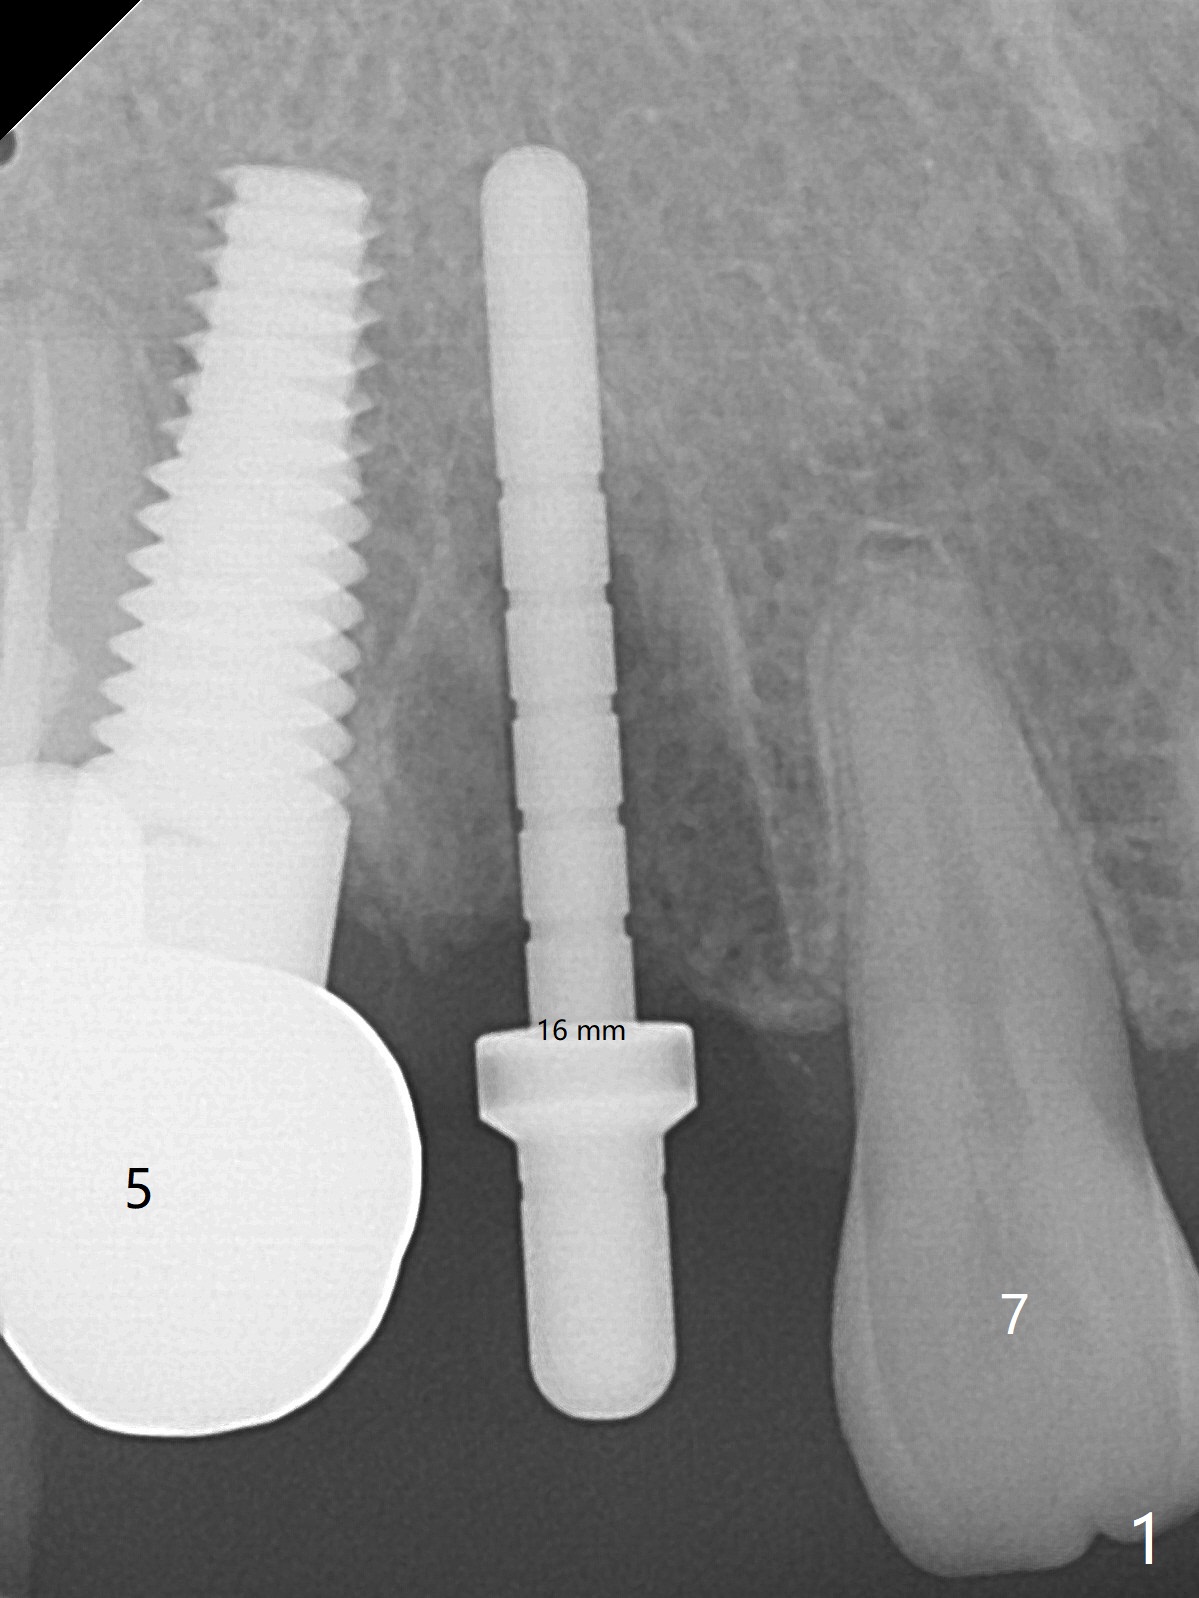

When the recemented crown at #6 is removed, the post is found to have been fractured. When the tooth is extracted, the socket walls are found intact. After moving the initial osteotomy (Fig.1) mesial, a 3.8x13 mm implant is placed (Fig.2). Clinically it appears supracrestal lingually. So the implant is placed deeper, but a cemented abutment is incompletely seated (Fig.3 <). When a longer abutment is used (easy grasping), it is seated completely (Fig.4). Then sticky bone is packed (Fig.5 *). When an immediate provisional is fabricated and seated, PRF membranes are inserted into the remaining gap between the gingiva and the provisional. Free hand surgery takes time and more intraop X-ray. It is inconvenient with nervous patients. The socket heals 2 weeks postop (Fig.6). The provisional will be next relined and reseated. It is difficult to insert gingival retraction cord 3.5 months postop because of the deep mesial margin. When an abutment with longer cuff is placed, the packing is easier (no biologic width violation, Fig.7 (^: resorbed mesial crest), as compared to Fig.5). When the crown is cemented (un-esthetic due to failure of use of temporary abutment), the metal shows at #5 with gingival recession because of buccal placement (Fig.8-10). Bone resorption is severe between #5 and 6 (Fig.7), as related to large gingival embrasure (Fig.9 *). When #5 crow is redone, move the gingival margin apical and fabricate provisional.